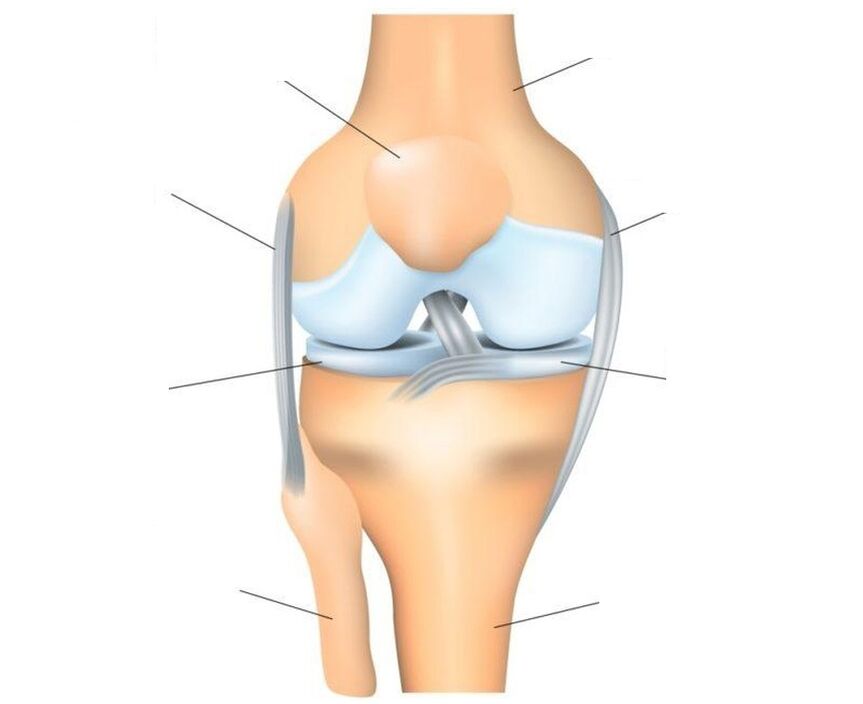

L'articolazione del ginocchio è l'articolazione più complessa, poiché sopporta il carico principale. Struttura: tre ossa (femore, tibia e rotula formano un'unica articolazione trocleare, costituita da due articolazioni interconnesse: femorotibiale (tibiofemorale) e femoro-rotulea (femorale rotulea).

La rotula è un osso sesamoide piatto (aggiuntivo nell'articolazione) che si attacca alla testa del femore, scorrendo nella sua scanalatura concava e fungendo da blocco. Caratteristiche strutturali: la superficie anteriore della rotula è ricoperta da periostio, la superficie posteriore, che si collega al femore, è ricoperta da cartilagine ialina. La rotula è rinforzata dai legamenti: principale e laterale – verticale (superiore e inferiore) e orizzontale (laterale – interno ed esterno).

O trasmette la forza del muscolo quadricipite femorale alle formazioni muscolo-scheletriche della parte inferiore della gamba, garantendo l'estensione della parte inferiore della gamba all'articolazione del ginocchio. La superficie delle ossa che formano le articolazioni è ricoperta di cartilagine, che funge da ammortizzatore. Ulteriori ammortizzatori che proteggono l'articolazione dalle lesioni sono due menischi cartilaginei a forma di mezzaluna situati tra il femore e la tibia. L'articolazione è mantenuta nella sua posizione corretta dai legamenti, dai tendini e dalla capsula circostante.

Lesioni e malattie colpiscono vari tessuti articolari. Non tutti possono ammalarsi. Pertanto, il tessuto cartilagineo non ha terminazioni nervose e quindi può essere distrutto in modo impercettibile e indolore. Ma i legamenti e la membrana sinoviale hanno molte terminazioni nervose e in caso di lesioni o processi infiammatori iniziano immediatamente a reagire, manifestandosi sotto forma di forti dolori. Con una significativa distruzione della cartilagine articolare, il dolore può essere associato al coinvolgimento del periostio, lo strato esterno dell'osso che ha una buona innervazione, nel processo.